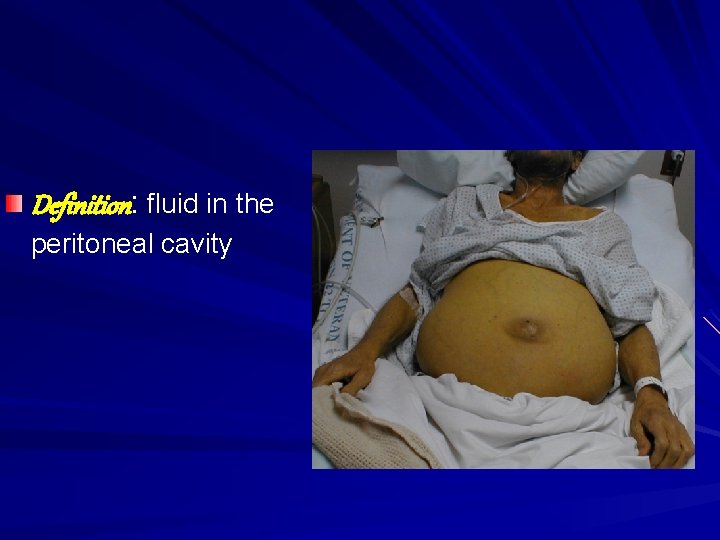

Ascites

Definition: fluid in the peritoneal cavity